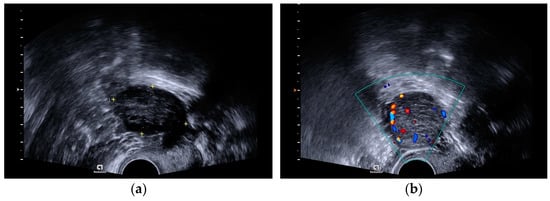

A transvaginal ultrasound scan revealed polycystic structured ovaries and a solid cystic formation of 32 × 31 mm size with strong blood flow in the left ovary (Figure 1a,b).

Figure 1.

(a) A transvaginal ultrasound scan showing a polycystic structured ovary. (b) A transvaginal ultrasound scan showing a left ovary tumor with strong blood flow.